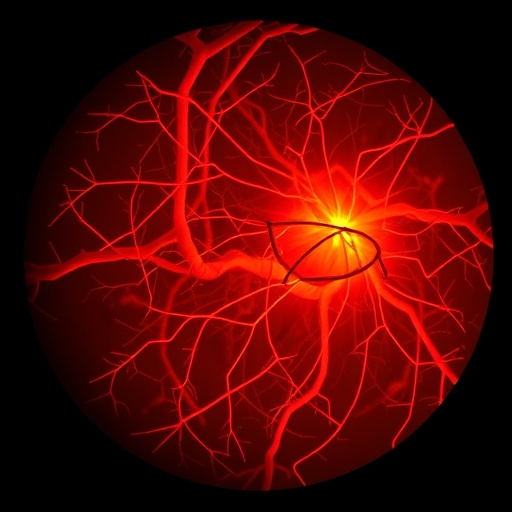

Revolutionizing Retinal Vessel Classification with Y-Net Networks